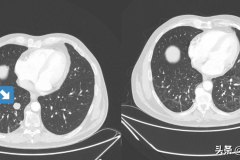

防疫科普:新冠肺炎真能“治愈”癌癥?這樣的案例再次發(fā)生了

防疫科普:新冠肺炎真能“治愈”癌癥?這樣的案例再次發(fā)生了

今年初,我們報(bào)道了一位霍奇金淋巴瘤患者,在感染新冠肺炎后腫瘤廣泛消退。不久前,類似的事情又發(fā)生了一例,這回是肺癌。